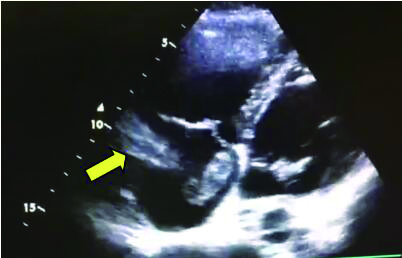

1 经典的挽救性溶栓治疗策略可能带给医生更多的是被动和难度例1 男性,28岁,体质量90 kg。主诉“胸闷、憋气1周加重1 d”。既往:体健;喜久坐(平均10~15 h/d);否认手术史、外伤史;入院查体:神志清楚,体温36.8℃,血压128/80 mmHg(1 mmHg=0.133 kPa),脉搏120次/min,呼吸26次/min,脉氧饱和度96%(安静,空气氧),未见明显乏氧征。双肺呼吸音清,未闻及干湿性啰音。心率120次/min,心律齐,P2 > A2,心界无扩大,无杂音。腹软,无压痛,肠鸣音正常,双下肢无浮肿。神经系统查体未见异常。血气分析(空气氧)提示pH 7.514,PaCO2 27.2 mmHg,PaO2 67.1 mmHg,SaO2 95.0%;D-Dimer:3 035 ng/mL,FDP 33.08 μg/mL,FBG 4.520 g/L;PLT 179.0 G/L,TNI 0.08 ng/mL,BNP 882.00 pg/mL;ALT 38 U/L,AST 17 U/L,CREA 82.6 μmol/L,血Na+、K+、Cl-正常范围;超声心动图(Ultrasonic Cardiogram,UCG)提示:右心增大,肺动脉主干及右肺动脉增宽,肺动脉主干32 mm,三尖瓣反流(重度),反流面积8.6 cm2,TI法估计SPAP为67 mmHg、左室舒末内径50 mm、左室E/A:45/38 cm/s, 左室壁厚度及运动正常,未见节段性室壁运动障碍;双下肢静脉超声提示左侧股静脉血栓形成可能(完全型)。心电图(图 1所示)提示窦性心动过速;肺动脉增强CT(Computed tomographic pulmonary angiography, CTPA)提示双肺主干明确充盈缺损(图 2所示)。入院诊断:急性肺血栓栓塞症(中高危)。入院后给予抗凝治疗(依诺肝素钠90 mg,皮下注射,1次/12 h)重叠华法令治疗的第4天D-Dimer升至47 482 ng/mL,第6天2 411 ng/mL。第7天常规复查双下肢超声未见新增血栓形成,复查UCG(当天INR 2.25)提示右心房漂浮血栓,并随心脏蠕动明显(图 3所示)。在准备胸外科手术取栓的过程中出现血压下降至70/40 mmHg,脉氧饱和度降至45%,立即给予气管插管并系统溶栓治疗(r-tPA 100 mg于2 h输注),溶栓治疗1.5 h患者血压逐渐回升并趋于稳定、溶栓治疗3 h自主呼吸开始恢复,于插管3天后(住院第10天)拔出气管插管,成功撤离呼吸机。溶栓过程中曾经出现消化道、气道出血,血红蛋白下降1.9 g/dL,未予输血治疗。溶栓后复查CTPA提示双肺主干血栓负荷明显减少,远段血液灌注明显增加(图 4所示)。

| 图 2 入院时CTPA提示双肺主干明确充盈缺损 |

| 图 4 溶栓后的CTPA肺动脉主干血栓负荷明显减少、远段血液灌注明显增加 |

患者特点及感悟:①该例患者是非常经典的中高危PE患者,抗凝治疗期间出现血流动力学不稳定并接受挽救性溶栓治疗的成功案例。患者入院时明确诊断为急性PE(中高危),生命体征稳定,按照指南指导下的抗凝治疗没有任何原则性问题。很有意思的问题是:住院后第1次D-Dimer 2 511 ng/mL,抗凝治疗的第4天D-Dimer升至47 482 ng/mL(>正常高限200倍),第6天降至2 411 ng/mL,住院期间患者并无任何不适,血压稳定,心率波动100~120次/min左右。入院第7天常规复查UCG提示右心房漂浮血栓。理论上讲,D-Dimer水平与血栓负荷成正比(纤溶系统正常),入院CTPA显示的血栓负荷量能否解释入院初D-Dimer?入院后第4天D-Dimer超过正常高限200倍时提示自身纤溶系统激活还是充分抗凝治疗期间依旧没有控制高凝状态导致持续新的血栓形成?当D-Dimer降至10倍高限时发现了新的血栓脱落至右心房。这样的结果提示急性期PE患者D-Dimer的巨大波动,高度提示有新发血栓形成的可能,应给予相应的检查,避免进一步血栓脱落出现致死事件发生。②右心房血栓的病死率报道36%,但是右心房血栓目前意见并不一致[7-9]。本例为抗凝达标(INR 2.25)时的发现右心漂浮血栓,原则上手术开胸取栓更为合理并可以避免栓子堵塞三尖瓣或肺动脉主干后导致猝死的发生。但因为准备手术期间,瞬间出现呼吸窘迫、氧合下降、血压骤降等危险时,被迫溶栓只能是一搏。很显然,这样的结果尚不能随意外推出后面的结论:一旦出现右心漂浮血栓都可以从系统溶栓治疗中获益。但至少说明治疗期间的密切的D-Dimer水平监测、定期的UCG检查和必要时的双下肢静脉超声检查有助于帮助医生进行准确的判断。③患者出现生命体征急剧恶化时,心率始终处于100~120次/min,对于青年患者而言虽然没有不适主诉,在排除其他原因的情况下,很可能成为预示病情存在潜在危险的信号。